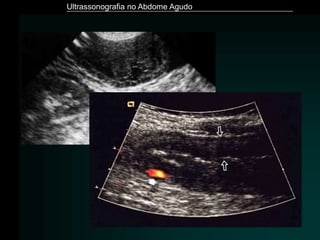

Pancreatite Aguda

• Exame de imagem de eleição - Tomografia Computadorizada

• ULTRASSONOGRAFIA

– Limitação - distensão gasosa

– Detecção de litíase biliar

– Aumento volumétrico

– Hipoecogenicidade difusa ou focal

– Dilatação do Wirsung

– Perda de definição dos limites

– Áreas hiperecogênicas – hemorragia

– Coleções – às vezes o único achado

Ultrassonografia no Abdome Agudo